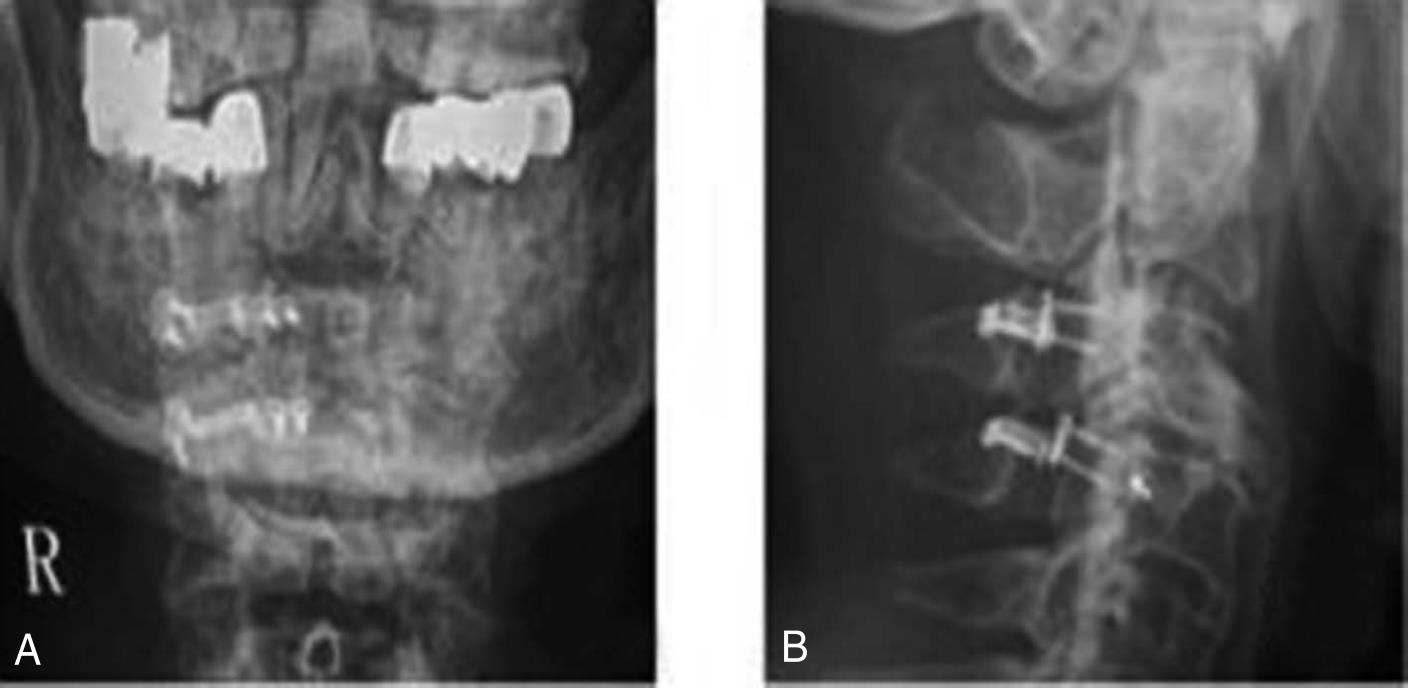

3.治疗概要 入院后完善相关检查,考虑超早期缺血性脑卒中。给予rt-PA替普酶静脉溶栓,24h后予抗血小板聚集等治疗,但效果欠佳,行头颅MRI+DWI显示双侧基底节区、双侧大脑半球白质多发腔隙性梗死,DWI序列未见急性梗死;脑白质稀疏、脑萎缩(图5-2)。入院第12天,左侧肢体肌力4级。追问患者有颈部疼痛史,否认有外伤史。遂行颈椎MRI平扫提示颈椎退行性变,C2/3、C3/4、C4/5、C5/6椎间盘突出,颈椎骨质增生;C3/4椎管狭窄,脊髓水肿,C3/4椎间盘层面脊髓损伤(图5-3)。于2016年5月21日至手术室行全麻气管插管下颈椎后路椎板切除+神经探查+侧块螺钉内固定急诊手术(图5-4),术中发现C3/4椎间盘突出。术后给予积极脱水、神经营养、激素冲击、改善循环等治疗后病情痊愈。

6.辅助检查:头颅CT未见明确梗死及出血灶(图5-1)。头颅MRI+DWI显示双侧基底节区、双侧大脑半球白质多发腔隙性梗死,DWI序列未见急性梗死;脑白质稀疏、脑萎缩;全副鼻窦炎,双侧下鼻甲肥大;双侧乳突窦炎。颈椎MRI平扫提示颈椎退行性变,C2/3、C3/4、C4/5、C5/6椎间盘突出,颈椎骨质增生;C3/4椎管狭窄,脊髓水肿,C3/4椎间盘层面脊髓损伤。

图5-2 头颅MRI+DWI序列未见高信号影